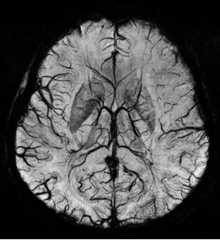

Sturge-Weber disease

An SWI venogram of a neonate with Sturge-Weber syndrome who did not display neurological symptoms is shown to the left. The initial conventional MR imaging methods did not demonstrate any abnormality. The abnormal venous vasculature in the left occipital lobe extending between the posterior horn of the ventricle and the cortical surface is clearly visible in the venogram. Due to the high resolution even collaterals can be resolved.